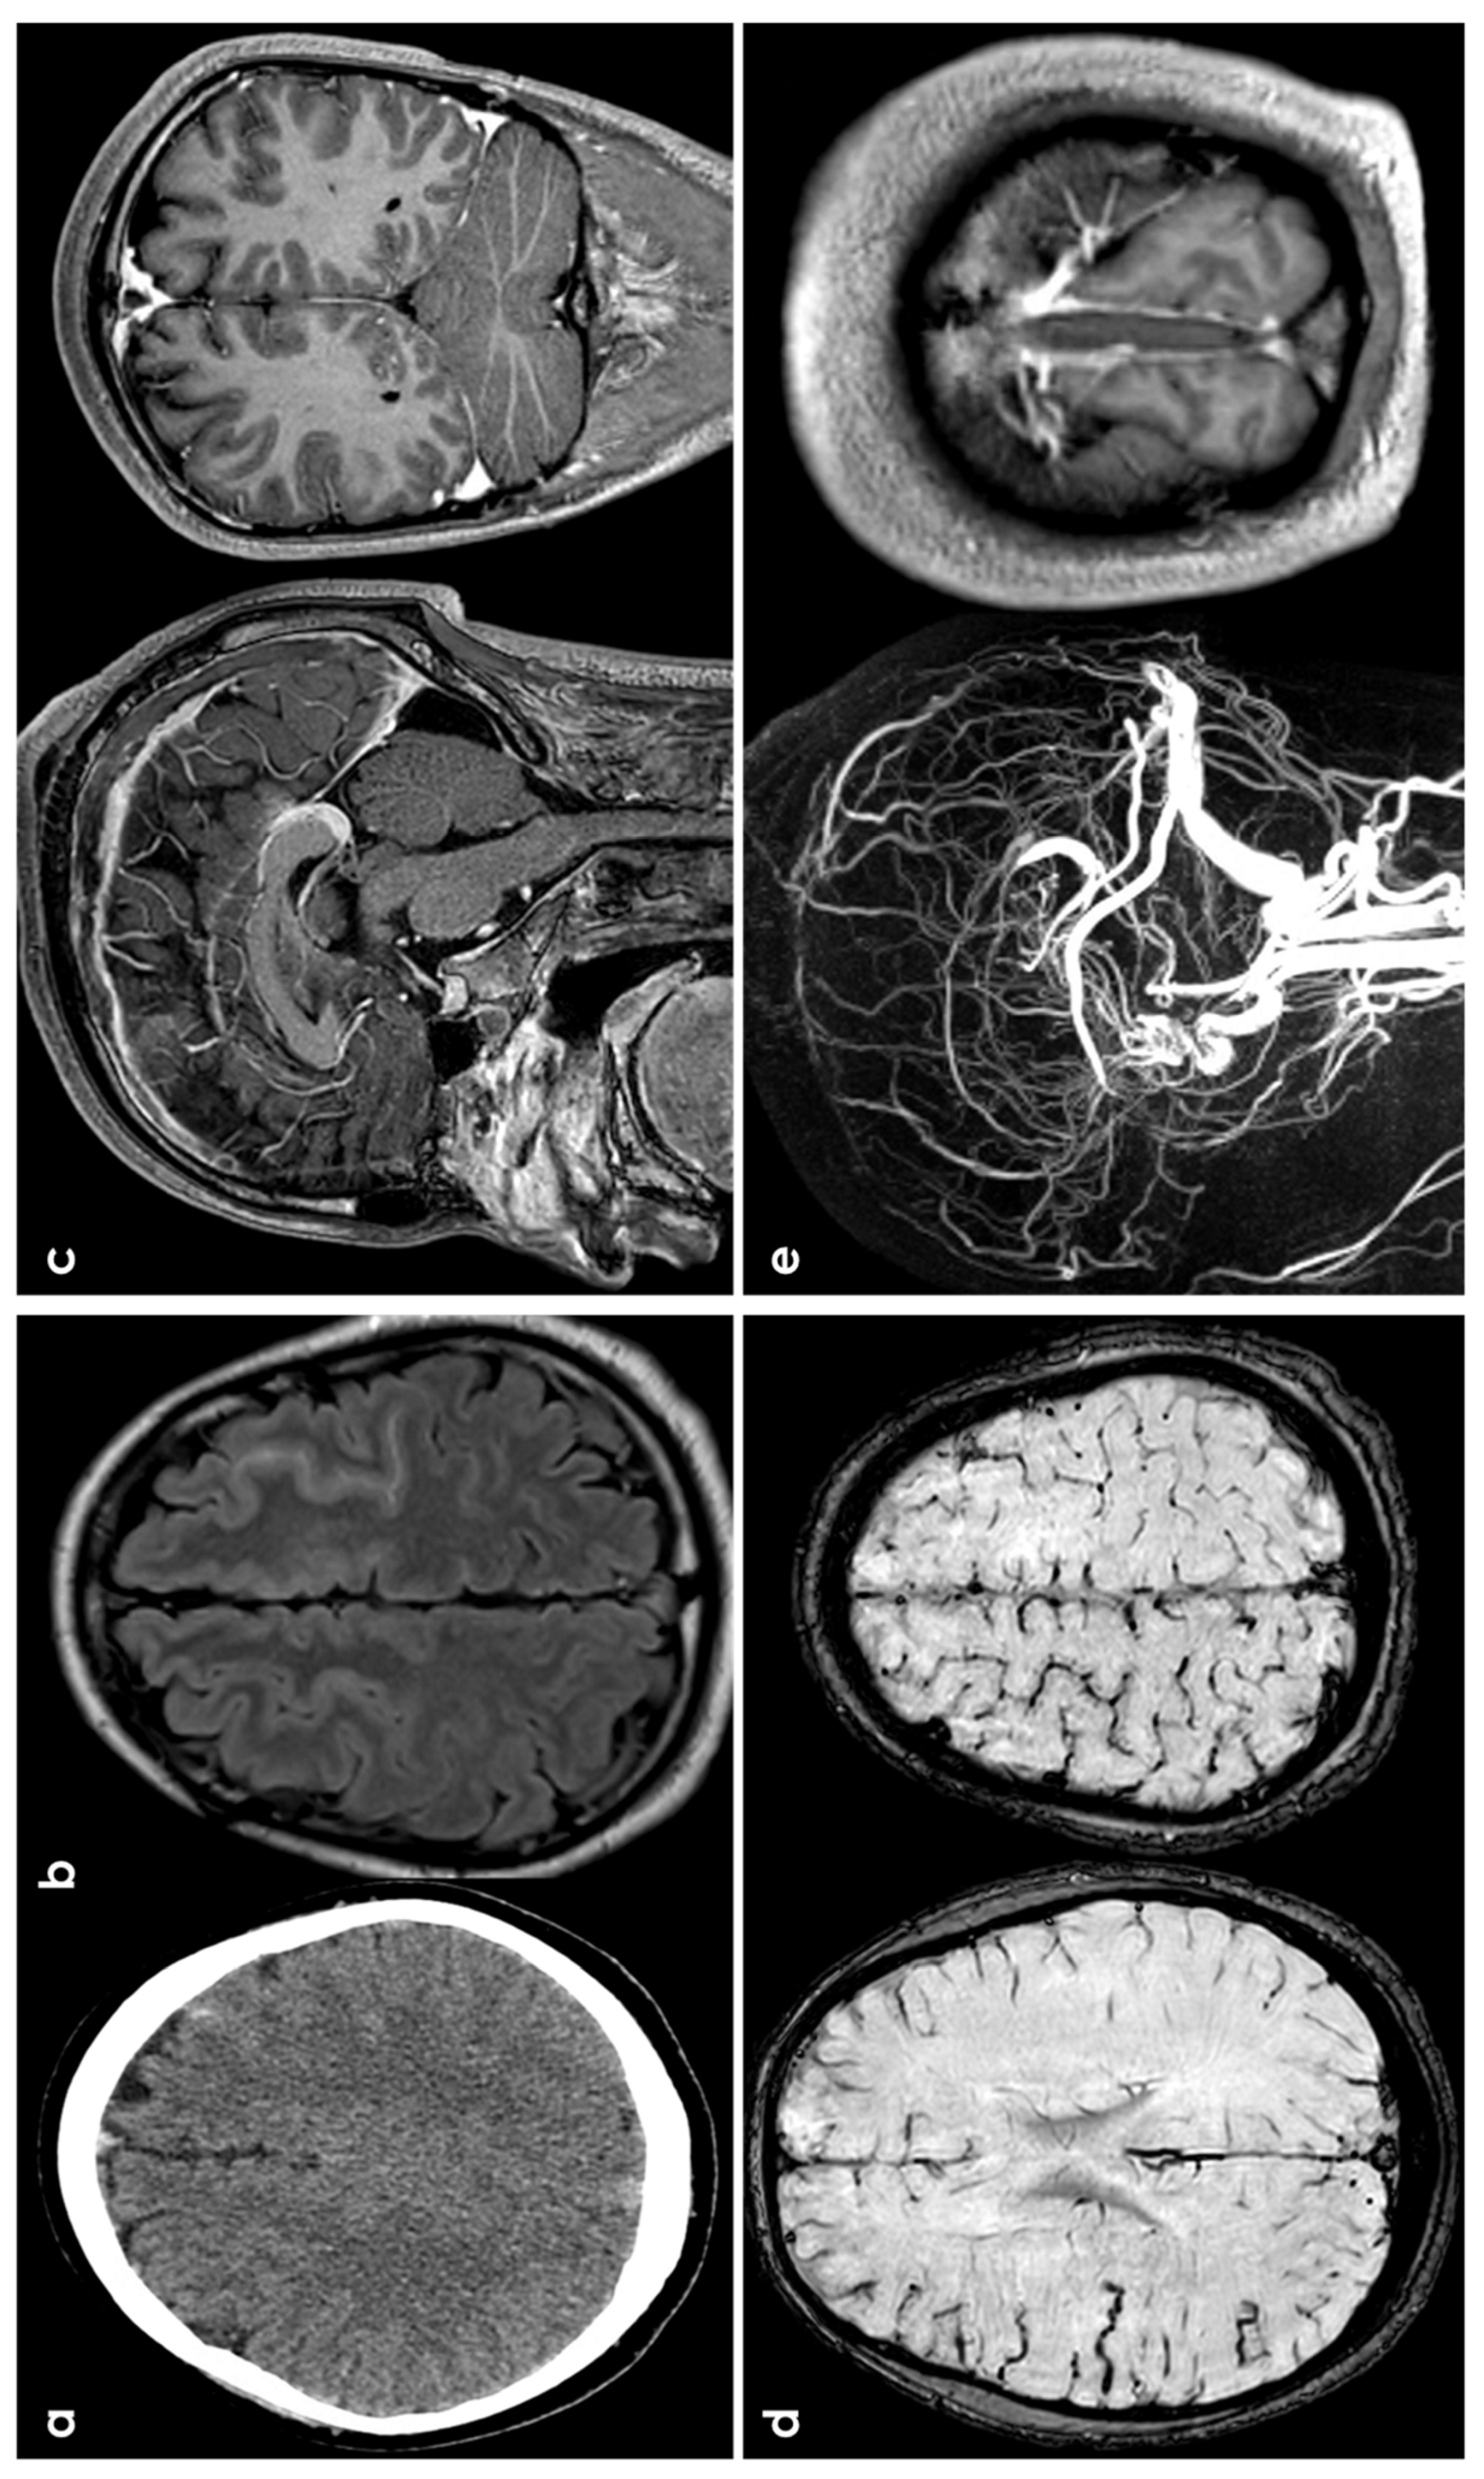

3.1. CAA

3.4. Cerebral Venous Thrombosis

3.5. Primary Central Nervous System Angiitis

3.6. PRES/RCVS